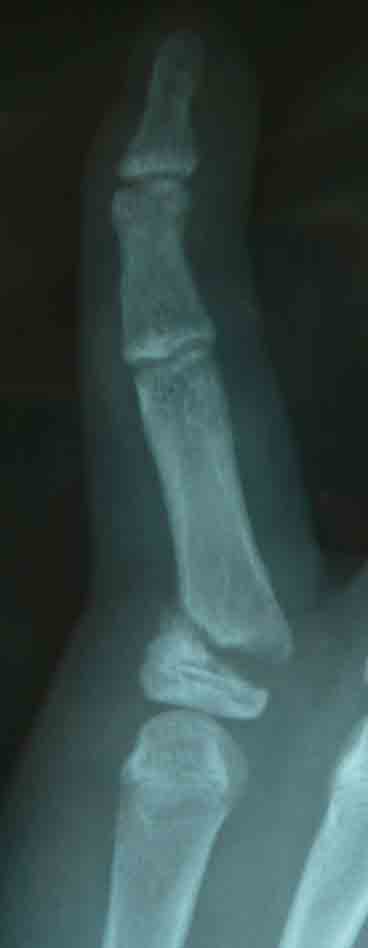

先日は、舟状骨骨折術後の抜釘について話題にしました。舟状骨では物理的に抜釘することが非常に難しいので施行していません。しかし、中節骨はどうでしょうか?

前腕部と異なり手指では軟部組織が薄いため、low profileな内固定材料とは言えども、ある程度は手指の可動域に影響を及ぼします。

抜釘術自体も物理的に難しくないため、手術を施行するメリットとデメリットを勘案すると、手指の骨折では抜釘術はアリかもしれません。